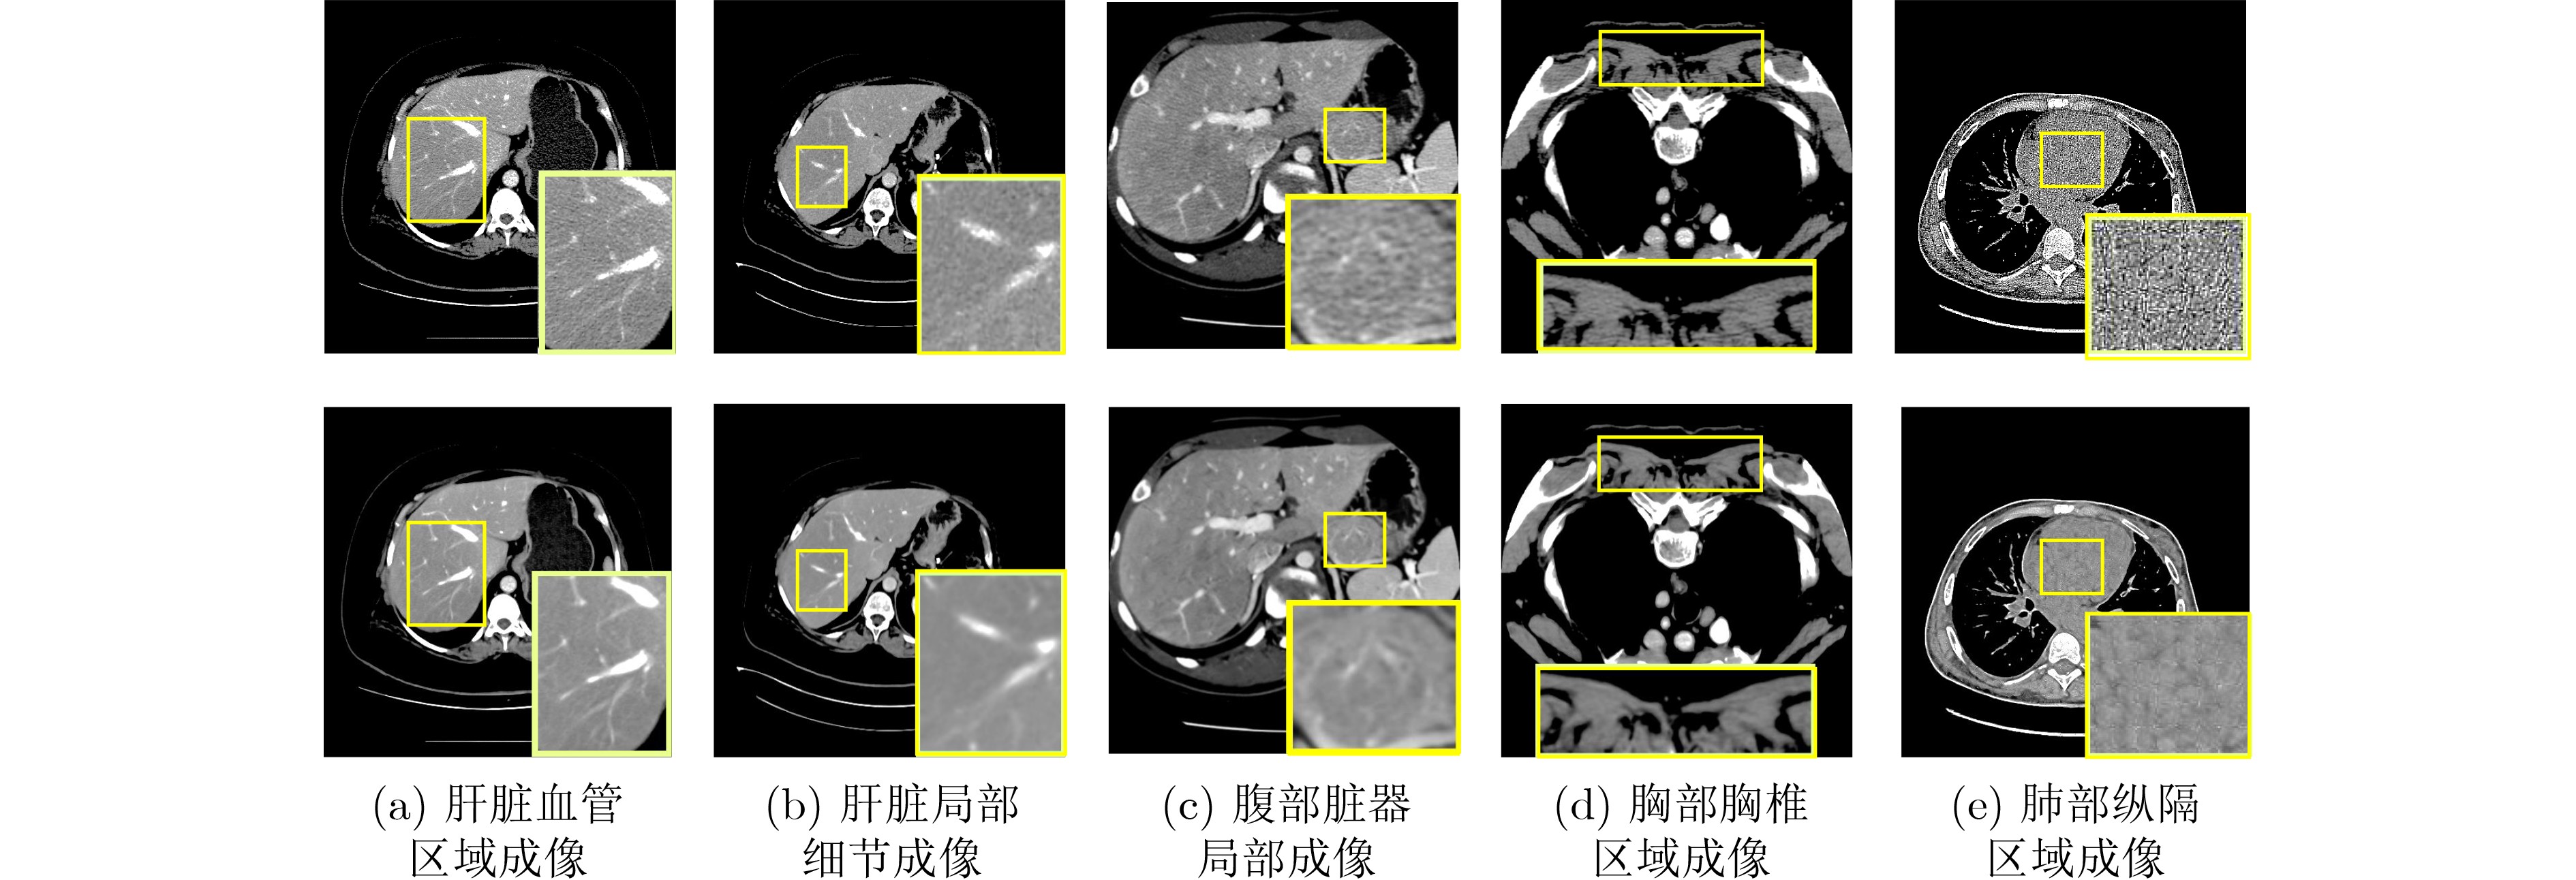

Objective Low-Dose Computed Tomography (LDCT) reduces patient radiation exposure but introduces substantial noise and artifacts into reconstructed images. Convolutional Neural Network (CNN)-based denoising approaches are limited by local receptive fields, which restrict their abilities to capture long-range dependencies. Transformer-based methods alleviate this limitation but incur quadratic computational complexity relative to image size. In contrast, State Space Model (SSM)–based Mamba frameworks achieve linear complexity for long-range interactions. However, existing Mamba-based methods often suffer from information loss and insufficient noise suppression. To address these limitations, we propose the Wave-MambaCT model. Methods The proposed Wave-MambaCT model adopts a multi-scale framework that integrates Discrete Wavelet Transform (DWT) with a Mamba module based on the SSM. First, DWT performs a two-level decomposition of the LDCT image, decoupling noise from Low-Frequency (LF) content. This design directs denoising primarily toward the High-Frequency (HF) components, facilitating noise suppression while preserving structural information. Second, a residual module combined with a Spatial-Channel Mamba (SCM) module extracts both local and global features from LF and HF bands at different scales. The noise-free LF features are then used to correct and enhance the corresponding HF features through an attention-based Cross-Frequency Mamba (CFM) module. Finally, inverse wavelet transform is applied in stages to progressively reconstruct the image. To further improve denoising performance and network stability, multiple loss functions are employed, including L1 loss, wavelet-domain LF loss, and adversarial loss for HF components. Results and Discussions Extensive experiments on the simulated Mayo Clinic datasets, the real Piglet datasets, and the hospital clinical dataset DeepLesion show that Wave-MambaCT provides superior denoising performance and generalization. On the Mayo dataset, a PSNR of 31.6528 is achieved, which is higher than that of the suboptimal method DenoMamba (PSNR31.4219 ), while MSE is reduced to0.00074 and SSIM and VIF are improved to0.8851 and0.4629 , respectively (Table 1 ). Visual results (Figs. 4 –6 ) demonstrate that edges and fine details such as abdominal textures and lesion contours are preserved, with minimal blurring or residual artifacts compared with competing methods. Computational efficiency analysis (Table 2 ) indicates that Wave-MambaCT maintains low FLOPs (17.2135 G) and parameters (5.3913 M). FLOPs are lower than those of all networks except RED-CNN, and the parameter count is higher only than those of RED-CNN and CTformer. During training, 4.12 minutes per epoch are required, longer only than RED-CNN. During testing,0.1463 seconds are required per image, which is at a medium level among the compared methods. Generalization tests on the Piglet datasets (Figs. 7 ,8 ,Tables 3 ,4 ) and DeepLesion (Fig. 9 ) further confirm the robustness and generalization capacity of Wave-MambaCT.In the proposed design, HF sub-bands are grouped, and noise-free LF information is used to correct and guide their recovery. This strategy is based on two considerations. First, it reduces network complexity and parameter count. Second, although the sub-bands correspond to HF information in different orientations, they are correlated and complementary as components of the same image. Joint processing enhances the representation of HF content, whereas processing them separately would require a multi-branch architecture, inevitably increasing complexity and parameters. Future work will explore approaches to reduce complexity and parameters when processing HF sub-bands individually, while strengthening their correlations to improve recovery. For structural simplicity, SCM is applied to both HF and LF feature extraction. However, redundancy exists when extracting LF features, and future studies will explore the use of different Mamba modules for HF and LF features to further optimize computational efficiency.Conclusions Wave-MambaCT integrates DWT for multi-scale decomposition, a residual module for local feature extraction, and an SCM module for efficient global dependency modeling to address the denoising challenges of LDCT images. By decoupling noise from LF content through DWT, the model enables targeted noise removal in the HF domain, facilitating effective noise suppression. The designed RSCM, composed of residual blocks and SCM modules, captures fine-grained textures and long-range interactions, enhancing the extraction of both local and global information. In parallel, the Cross-band Enhancement Module (CEM) employs noise-free LF features to refine HF components through attention-based CFM, ensuring structural consistency across scales. Ablation studies ( Table 5 ) confirm the essential contributions of both SCM and CEM modules to maintaining high performance. Importantly, the model’s staged denoising strategy achieves a favorable balance between noise reduction and structural preservation, yielding robustness to varying radiation doses and complex noise distributions.-